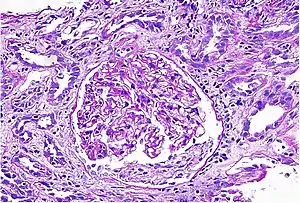

Acute interstitial nephritis on light microscopy

While non-invasive patient evaluation (physical examination, blood and urine testing, imaging studies) can be suggestive, the only way to definitively diagnosis interstitial nephritis is with a tissue diagnosis obtained by kidney biopsy. Pathologic examination will reveal the presence of interstitial edema and inflammatory infiltration with various white blood cells, including neutrophils, eosinophils, and lymphocytes. Generally, blood vessels and glomeruli are not affected. Electron microscopy shows mitochondrial damage in the tubular epithelial cells, vacuoles in the cytoplasm, and enlarged endoplasmic reticulum.[21]